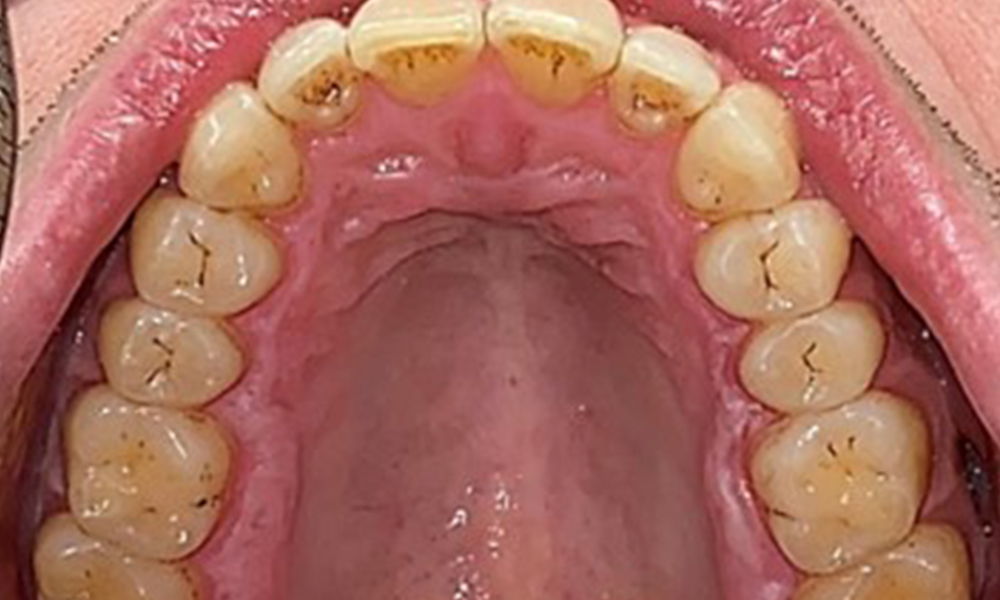

Vue occlusale du maxillaire.

Fig. 3: Vue occlusale du maxillaire, © Dr R. Krapf

Le patient a une dentition complète avec un total de 28 dents. Il y avait des érosions et des attritions notables. (Fig. 4, Fig. 5). En raison du bruxisme, le patient a porté pendant de nombreuses années une attelle avec une gouttière ajustée la nuit. Les érosions ont été causées par une consommation prolongée de boissons isotoniques. Aucune perte d'os parodontal ou carie active n'a été observée.